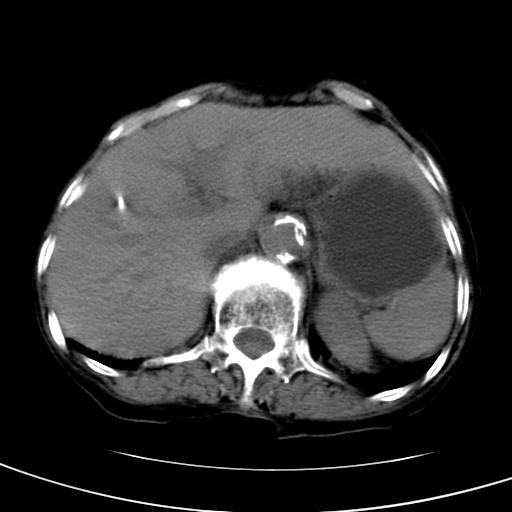

以下是引用wolft在2008-3-5 12:30:00的发言:[br]肝脏未见明显肿块影,但肝左叶增大,跨越腹中线到达脾胃前,且有一血管过去,考虑为先天变异:獭尾肝,胆囊为慢性胆囊炎急发,但胰腺头颈部有增大,密度不均匀,应该ct增强一下。

以下是引用zjzjr在2008-3-5 16:41:00的发言:[br]1.考虑慢性胰腺炎急性发作,建议增强除外占位性病变.[br]2.胆囊结石伴胆囊炎.[br]3.肝内胆管结石.